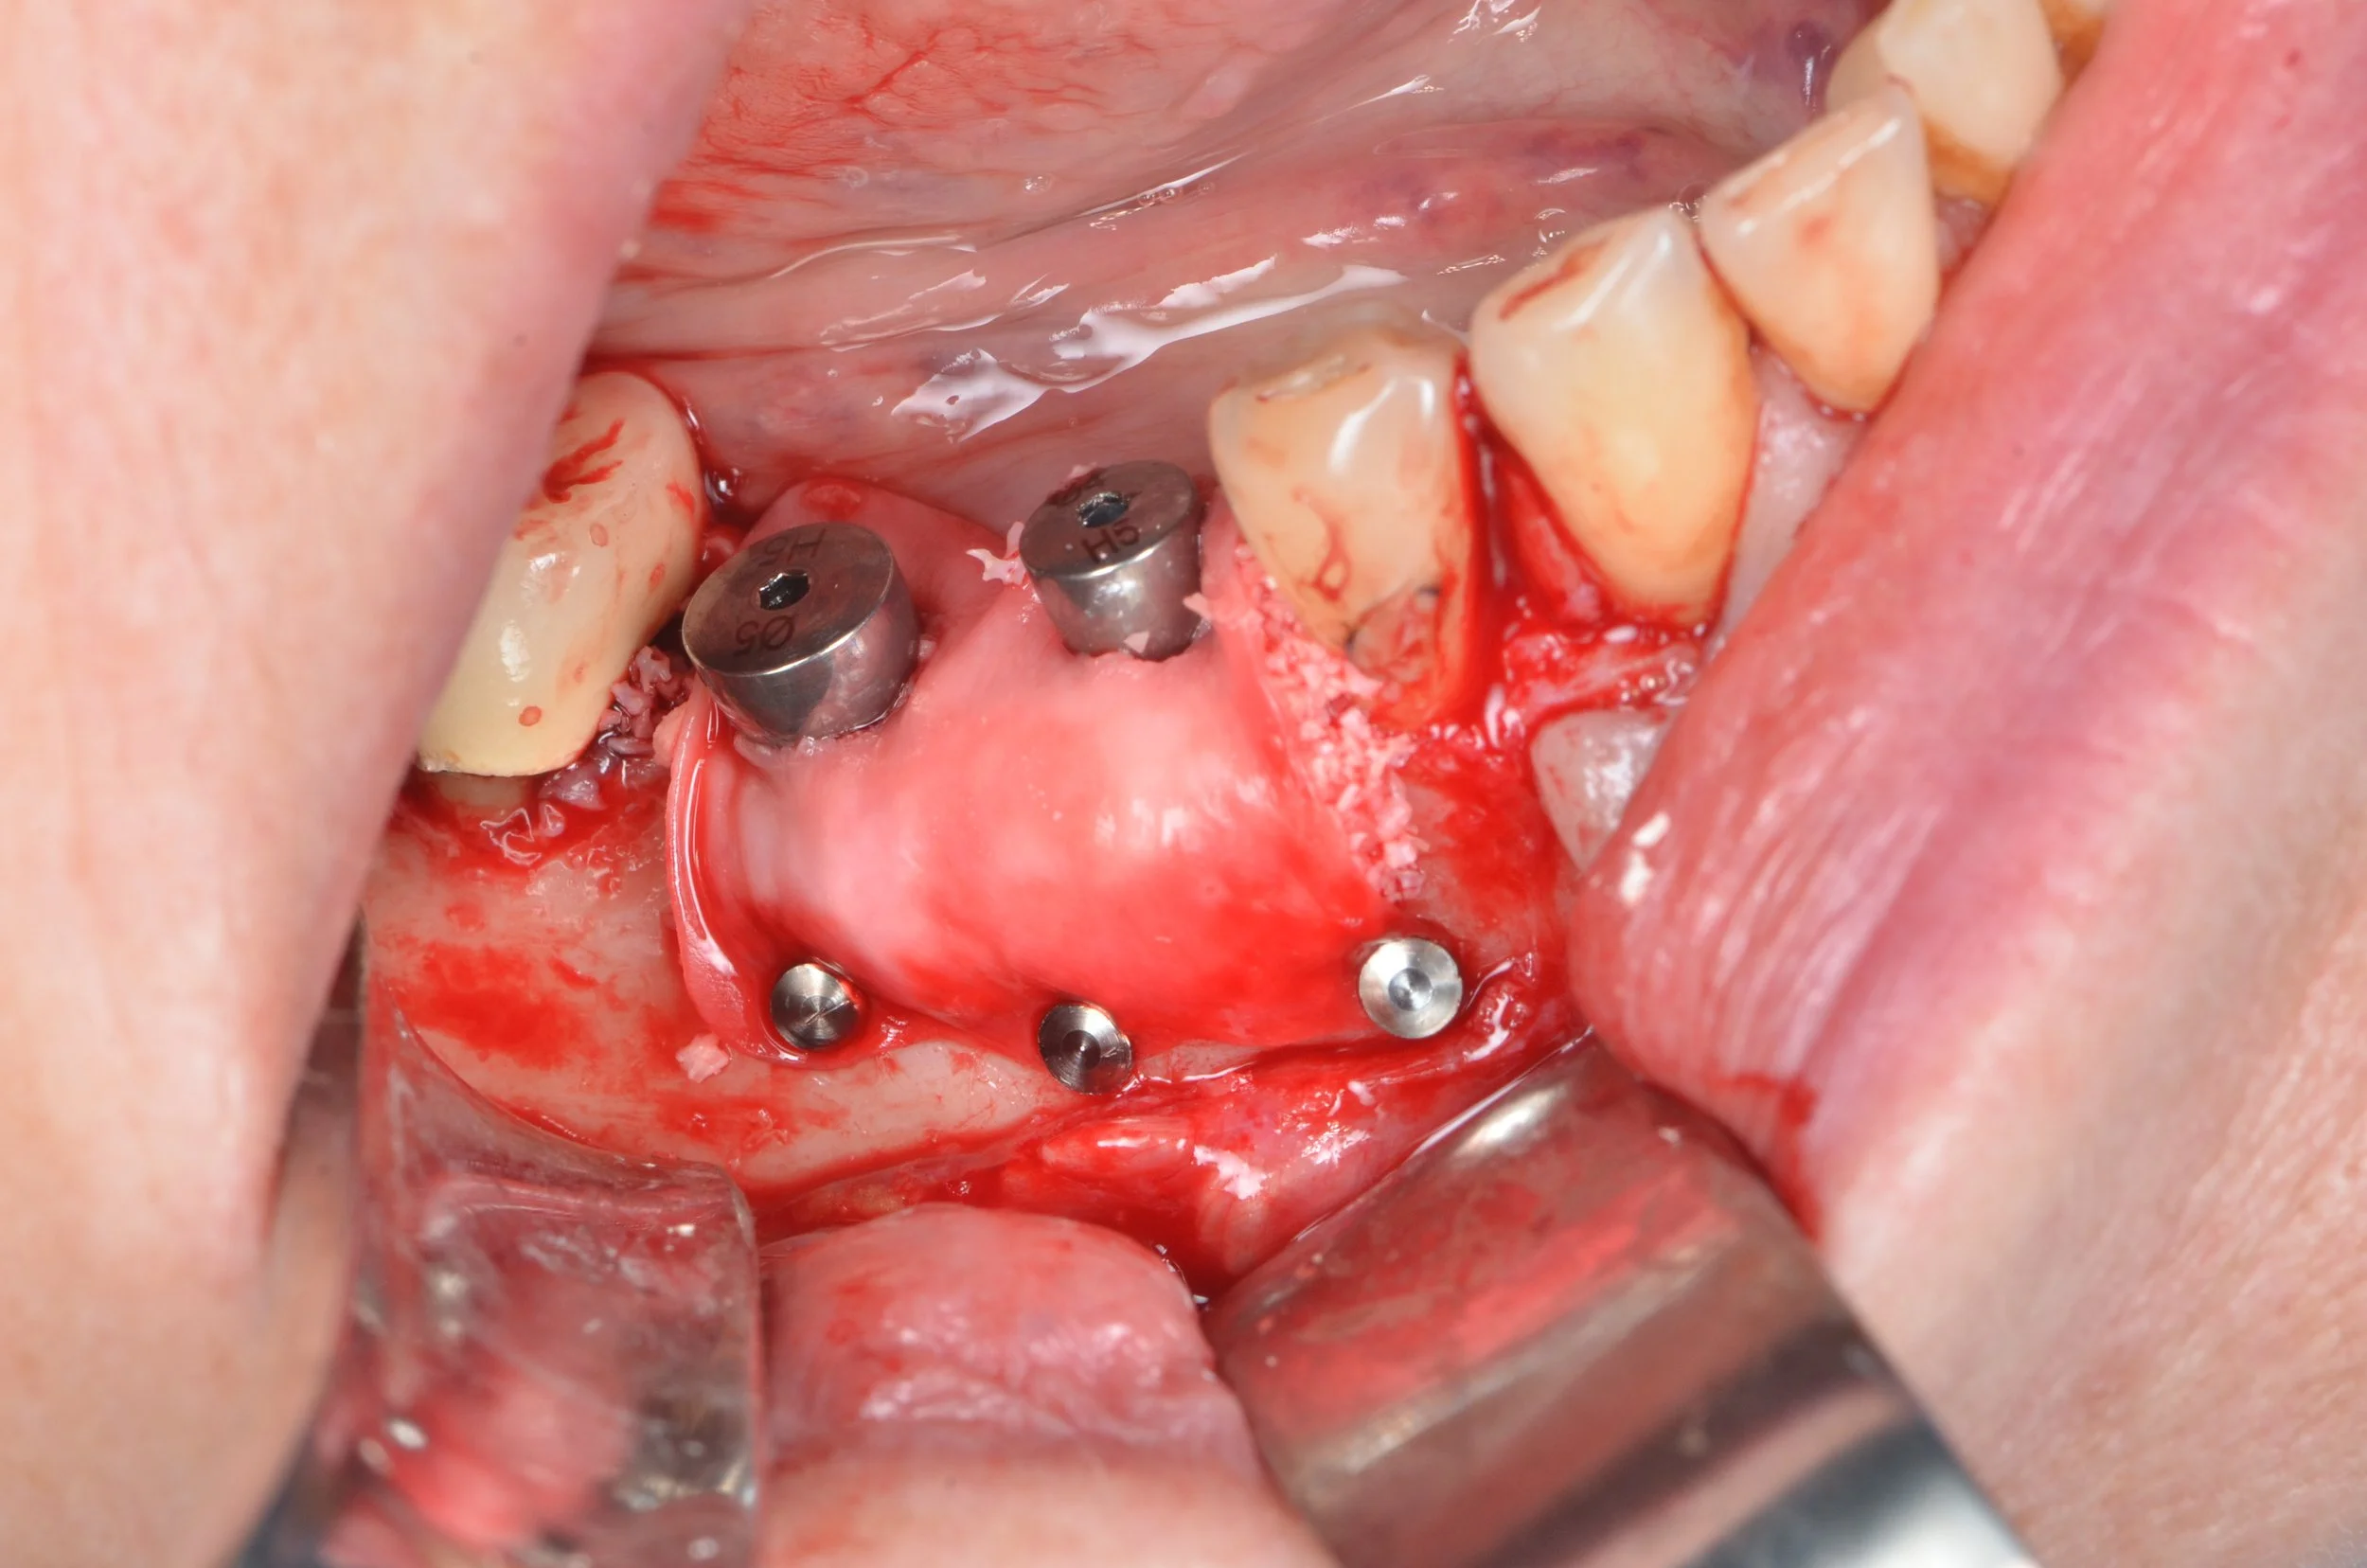

Simplification des protocoles opératoires en chirurgie implantaire et pré implantaire

Longtemps perçues comme des disciplines réservées à une élite en raison de leur technicité et des risques associés, la chirurgie implantaire – et plus encore pré-implantaire – ont été abordées sous un angle nouveau : celui de la simplification, de l’accessibilité et de la maîtrise des protocoles.

Une approche concrète, pragmatique, tournée vers la pratique quotidienne des chirurgiens.